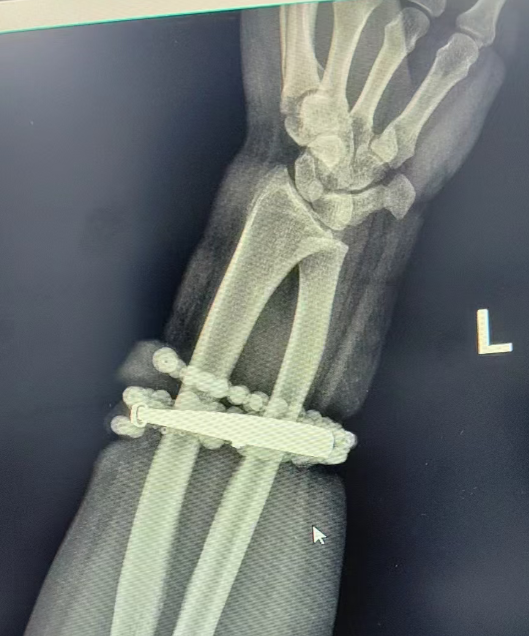

然而,就在兩周前,龔女士的情況急轉直下:手腕不僅疼痛加劇,還出現(xiàn)了明顯的紅腫,甚至有膿液滲出。她這才驚覺——手鐲和串珠,已經有一部分“長”進了肉里,根本取不下來了!

“這是典型的首飾長期壓迫、摩擦,加上細菌感染,引發(fā)的慢性炎癥和肉芽組織增生。”醫(yī)生介紹,此時,手鐲和串珠已經成了一個不斷刺激皮膚、污染傷口的“病灶”,如果不盡快手術取出,感染可能進一步擴散,甚至危及生命或影響手臂功能。

經過一個多小時的手術,醫(yī)生們將手鐲和串珠從厚厚的增生組織中完整剝離出來。目前,龔女士恢復良好,已順利出院。